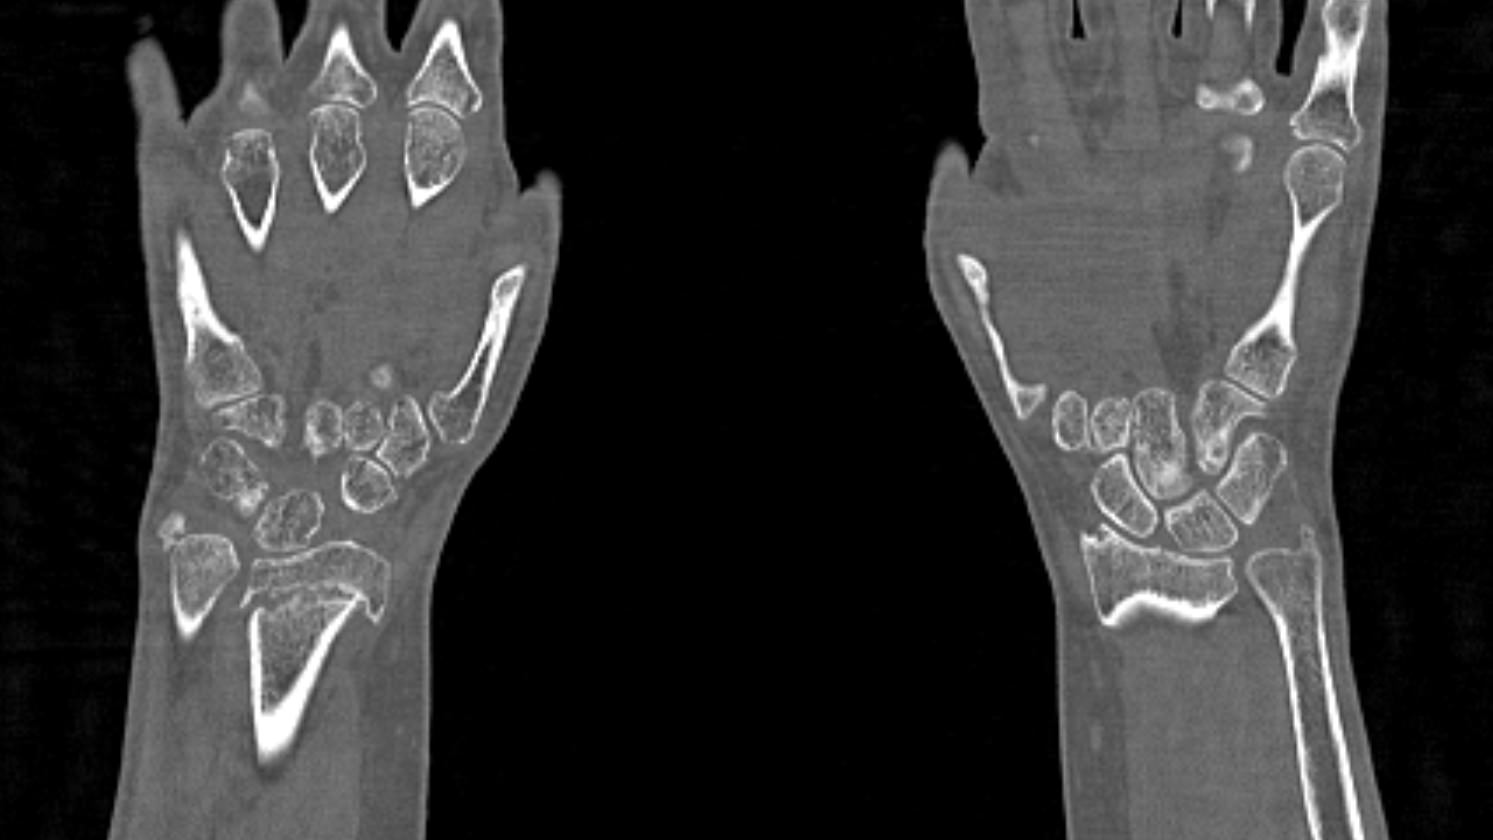

Метод КТ основан на использовании ионизирующего излучения и способности тканей поглощать рентгеновские лучи. Костные ткани обладают высокой плотностью и способны активно поглощать рентгеновские лучи, поэтому они хорошо видны на снимках КТ. В отличие от обычного рентгена компьютерный томограф послойно сканирует исследуемую область в нескольких плоскостях, благодаря чему получаются снимки в мельчайших подробностях. Затем с помощью цифровой обработки данных, полученных при КТ-сканировании, создаются трехмерные модели области исследования.

Таким образом мультиспиральная компьютерная томография позволяет оценить состояние всех структур лучезапястного сустава, выявить травматические повреждения, признаки воспалительных заболеваний, диагностировать аномалии развития и опухолевые образования. При травмах на снимках и трехмерных изображениях хорошо видны фрагменты костных отломков, эти данные используются при подготовке к оперативным вмешательствам. После операции результаты КТ позволяют оценить правильность репозиции костных структур, выявить послеоперационные осложнения, отследить в динамике процесс восстановления тканей.